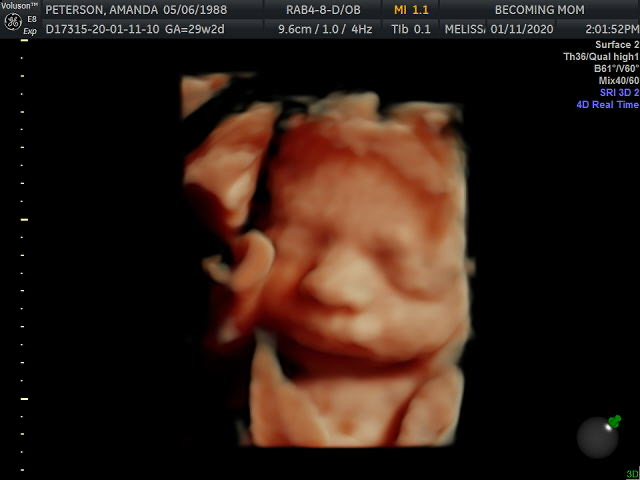

Hands down, the best part of this week was getting to see our baby girl via 3D/4D Ultrasound! Justin bought me a session at Becoming Mom as a Christmas gift, so he, my mom and I went on Saturday to see our sweet girl.

A friend from high school works there, and when I checked in, the man at the desk handed me a pink unicorn stuffed animal and said, “Your friend sent this.” I was like, Huh?? and looked at Justin, thinking he might have added it as part of the gift, but he looked just as confused as I was. Sami had sent it! During our visit, the technician recorded the baby’s heartbeat and placed it inside the unicorn as a keepsake. Sami, if you’re reading, thank you so much!!!

In addition to the unicorn, we got 26 photos and a video as a result of our visit (which I promptly forwarded on to all our family members and a few friends!). Her hand and her knee were up by her face the entire time, and the technician kept poking my belly to get her to move them. She would oblige, for two seconds, and then bring them right back up. Stubborn girl!

Overall, our experience at Becoming Mom was phenomenal, and our technician, Melissa, was so sweet and patient. I would absolutely recommend this company to any of my pregnant readers.

I am so obsessed with her little squishy nose and those cheeks!!! I can hardly believe that this precious face is a product of Justin and me. Reproduction is incredible. She’s so perfect, and now I’m even more anxious to meet her.